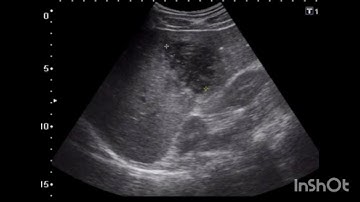

67. NLP Based Identification of NAFLD through Radiology Reports